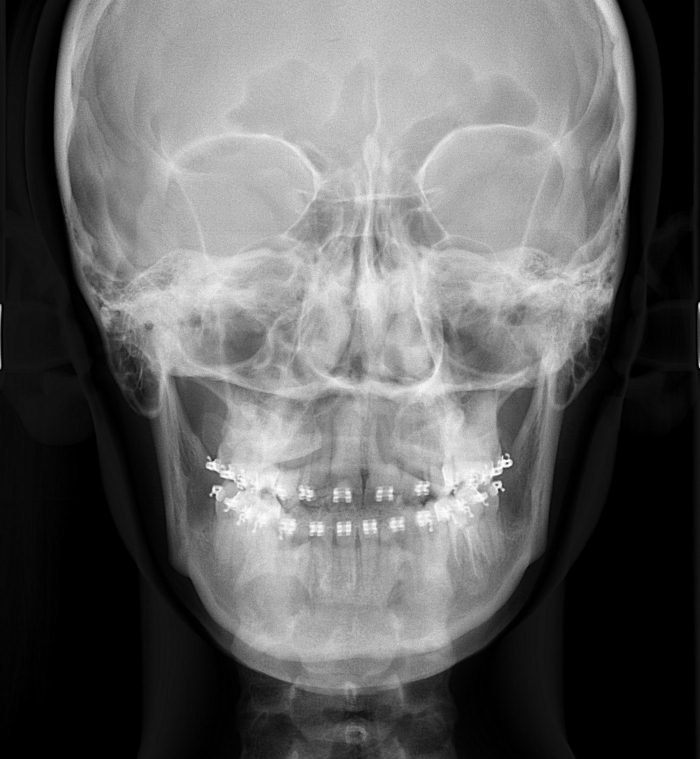

Telerradiografia frontal inicial  - Clínica Cliniface

Telerradiografia frontal inicial